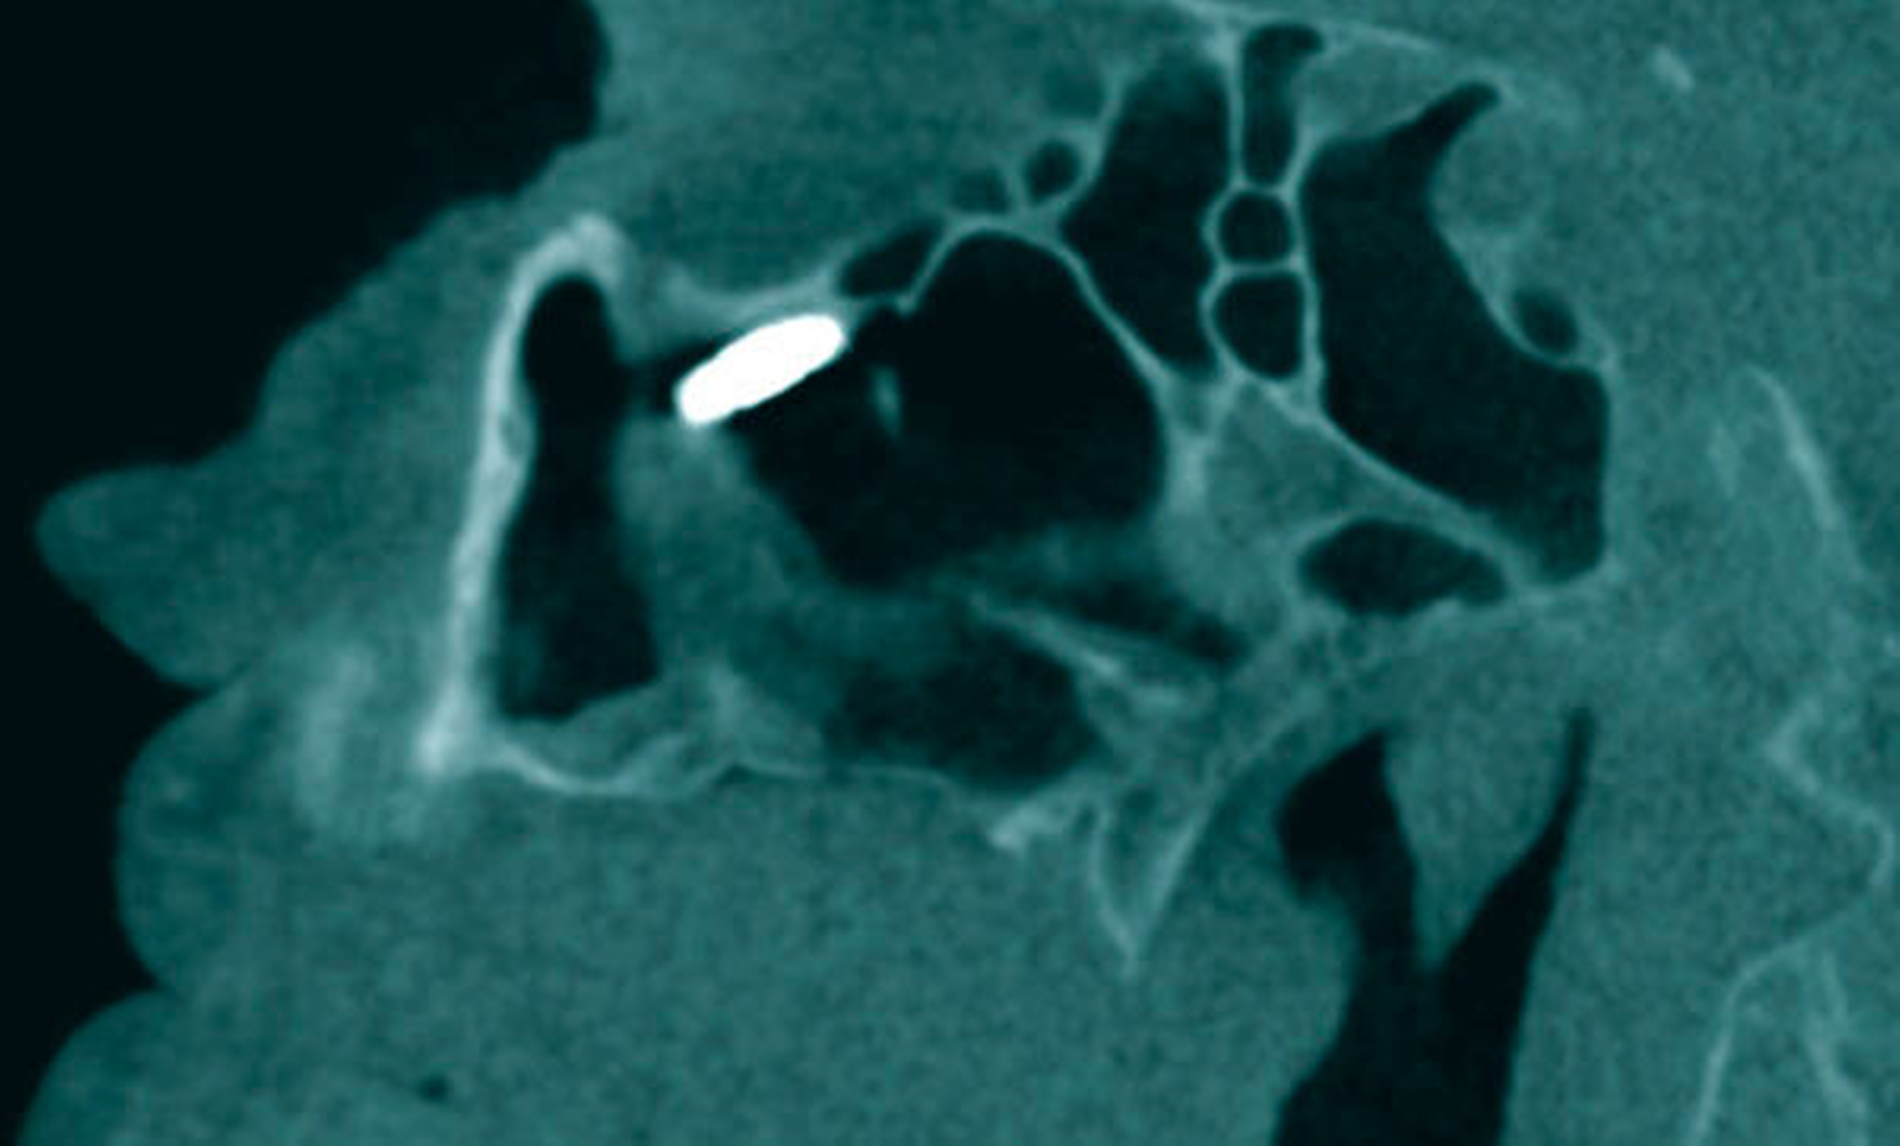

Es folgte die Planung zur operativen Entfernung des Fremdkörpers in Intubationsnarkose über ein enorales Fenster zur Kieferhöhle. Nach Präparation eines mukoperiostalen Lappens über einen marginalen Zahnfleischrandschnitt wurde minimalinvasiv mittels Piezosurgery® (mectron, Köln) ein Knochenfenster zur Kieferhöhle angelegt. Mit dem Endoskop (30grad Optik, Karl-Storz, Berlin) zeigte sich das Ostium naturale offen und frei von dem radiologisch hier lokalisierten Fremdkörper. Dieser befand sich nun im Kieferhöhlenboden (Abbildung 3) und ließ sich komplikationslos bergen (Abbildung 4). Die Wunde wurde mehrschichtig geschlossen.